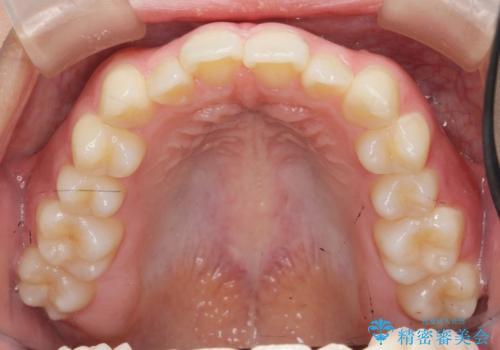

ガタつきの改善 マウスピース矯正治療

- 歯のがたつきの改善を求めて、矯正治療を希望され来院されました。

少量の歯のディスキング、歯列弓拡大、アタッチメントを装着することで審美的な歯列へとマウスピース矯正インビザラインを用いて治療を行います。

マウスピース矯正は装着時間の遵守が非常に大切ですが、しっかりと20時間/日以上の装着を守っていただいたおかげで良好な治療結果を得ることができました。